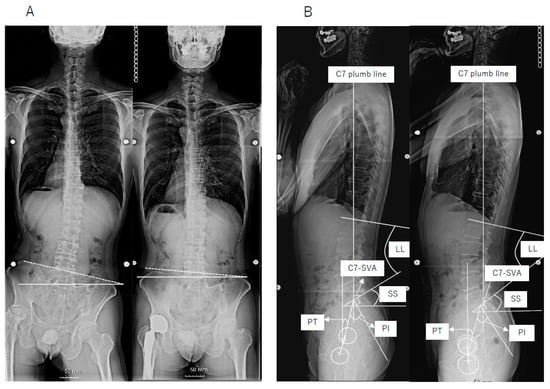

2. Materials and Methods

3. Results

4. Discussion